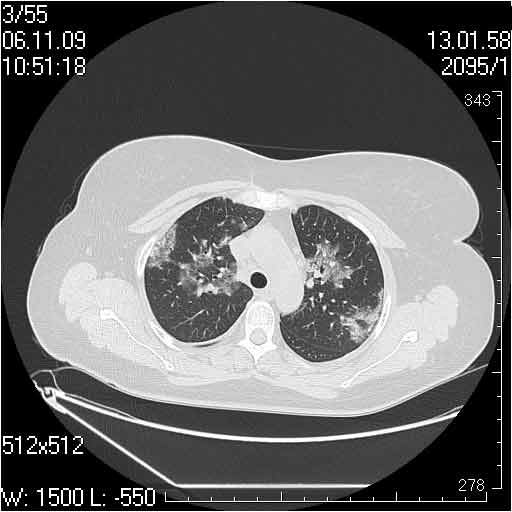

Случай №1

Женщина 50 лет.

Случай 1: изменения характерны для интерстициальной пневмонии (IIP/UIP idiopathic interstitial pneumonia/usual interstitial pneumonia); говорить о конкретной форме без открытой биопсии затруднительно.